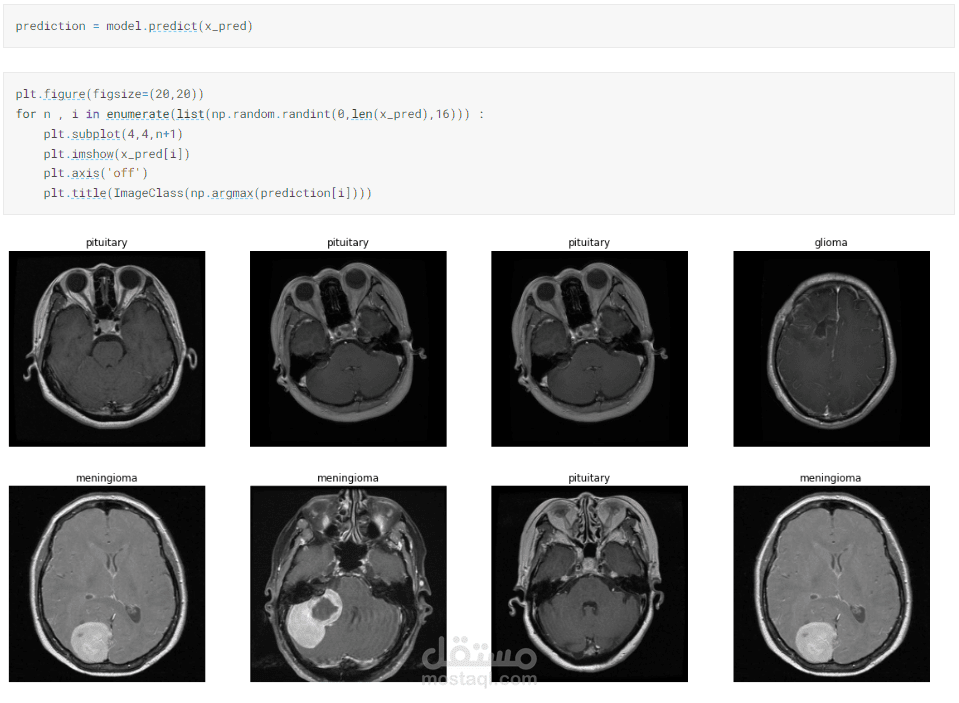

عمل نماذج تعلم الالي و التعليم العميق باستخدلم ( Keras ,Tensorflow ) و تدريب الmodels و تحسين ال accuracy

عمل model deep learning

عمل شغل computer vision